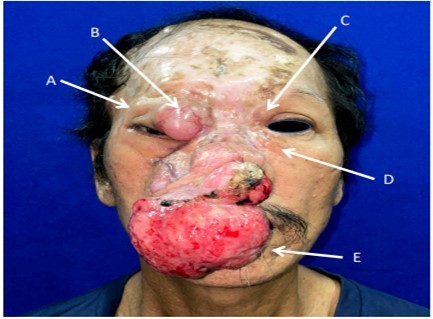

On ophthalmologic examination, the best-corrected visual acuity (BCVA) for the right eye was 6/7.5 and 6/6 for the left eye. There was no proptosis on Hertel’s exophthalmometry. On the right upper eyelid, a 3x3x1.8 cm erythematous firm mass with telangiectatic vessels was visualized and palpated on the nasal area and a 1.1x0.9x1.0cm non-erythematous mass, firm, non-tender, mass was noted on the temporal area. The medial posterior lamella of the right lower lid appeared to be thickened. On the left upper eyelid, there was a 1.5x1.5cm soft, non-tender, nodular mass. A 1.7x1.5cm nodular, firm, rubbery mass was also noted on the medial aspect of the left lower eyelid. Eye motility was normal, and pupils were symmetric with no afferent pupillary defect. Intraocular pressures were normal, no abnormalities on anterior and posterior segment examination. On palpation, there was a left submandibular lymphadenopathy. Facial, Cranial, and Orbital MRI noted an 8.6 x 7.3 x 6.0 cm (CCxWxAP) lo bulated, fungating mass arising from the right nasal region exhibiting isointense signals on T1-W and hypertintense to muscle in T2-W. The mass showed avid enhancement on postcontrast scans. The mass extended into the right nasal cavity and was intimately related to the inferior turbinate. Posteriorly, the mass appeared to involve the medial aspect of the right maxillary bone. A lobulated,fungating mass arose from the medial right intraorbital extraconal region measuring approximately 3.2 x 3.3 x 4.5 cm. This was also isointense on TW1, and hyperintense to muscle on T2W similar to the nasal mass and intimately related to the medial aspect of the globe and medial rectus muscle. The orbicularis oculi muscle on the right was not delineated. Medially, the mass was bounded by the lamina papyracea. Multiple smaller similar-looking subcutaneous foci are Figure 1. Preoperative picture showing the extent of lesions. (A) 1.0x0.9x1.0cm firm, non-tender mass (B) 3.0x3.0x1.8cm soft, erythematous, telangiectatic mass (C) 1.5x1.5cm soft, non-tender, nodular mass (D) 1.7x1.5cm firm, rubbery, nodular mass (E) 8.6x7.3x6.0cm firm, fungating nasal mass excised by ORL service.

Figure 1.Preoperative picture showing extent of lesions. (A) 1.0x0.9x1.0cm firm, non-tender mass (B)3.0x3.0x1.8cm soft, erythematous, telangiectatic mass (C) 1.5x1.5cm soft, non-tender, nodular mass (D) 1.7x1.5cm firm, rubbery, nodular mass (E) 8.6x7.3x6.0cm firm, fungating nasal mass excised by Otorhinolaryngology service